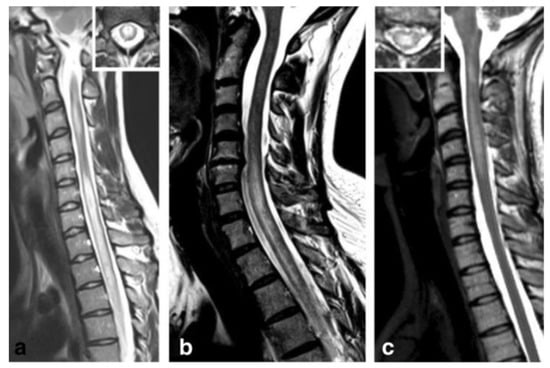

| Brain MRI | Dawson fingers, lesions perpendicular to ventricles Cortical/yuxtacortical lesions Perivenular Nodular or ring/open-ring enhancing lesions Unilateral short optic nerve enhancement | Subcortical or deep gray matter bilateral, sometimes poorly-defined Simultaneous enhancement with gadolinium | Periependimal lesions Tumefactive lesions Involvement of corticospinal tract Marked enhancement, ‘cloud like’ Bilateral, long optic nerve enhancement | Non—specific supratentorial subcortical or small deep white matter foci. Occasionally T2 lesions in brainstem, and infratentorial regions Anterior bilateral ON with perineural optic nerved enhancement | Linear radial periventricular contrast enhancement pattern |

| Spinal cord MRI | Small, peripheral, posterolateral lesions Less than 3 segments Gadolinium enhancement during acute phase | LETM or multiple short segment myelitis Edematous lesions and gadolinium enhancement in acute phase | Central LETM Edematous Necrosis or cavitation Gadolinium enhancement in acute phase | LETM or short myelitis, frequent conus medullaris involvement Linear gadolinium enhancement of the ependymal canal | LETM Central lesions |